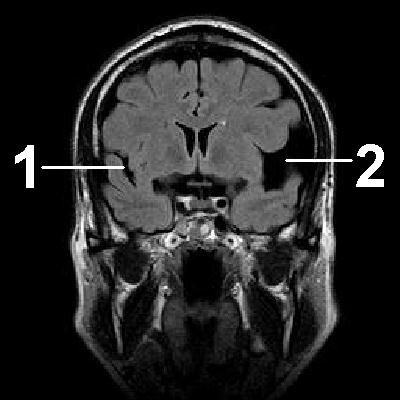

Клиника арахноидальной кисты не имеет специфичных проявлений и соответствует клинической картине, общей для большинства объемных образований головного мозга. К последним относятся внутримозговые и оболочечные гематомы, первичные и метастатические опухоли мозга, абсцесс головного мозга, внутримозговая киста. Осмотр невролога и первичное неврологическое обследование (электроэнцефалография, реоэнцефалография и эхо-энцефалография) позволяют установить наличие интракраниального образования с внутричерепной гипертензией и существующую судорожную активность головного мозга. Для уточнения характера объемного образования и его локализации необходимо проведение МРТ, СКТ головного мозга или КТ.

Оптимальным диагностическим методом для распознавания арахноидальных кист выступает МРТ головного мозга с контрастированием. Использование контрастных веществ позволяет отдифференцировать кисту от опухоли головного мозга. Основным критерием арахноидальной кисты, отличающим ее от опухоли, является отсутствие способности накапливать контраст. При помощи МРТ проводится дифференциальная диагностика с субдуральной гематомой, субарахноидальным кровоизлиянием, субдуральной гигромой, абсцессом, инсультом, энцефалитом и тд церебральными заболеваниями.